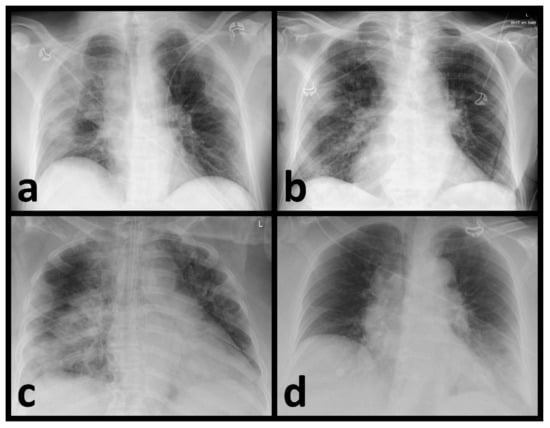

3.2. Identification of Pneumonia by Radiologists

3.3. AI-Based Diagnostic Performance